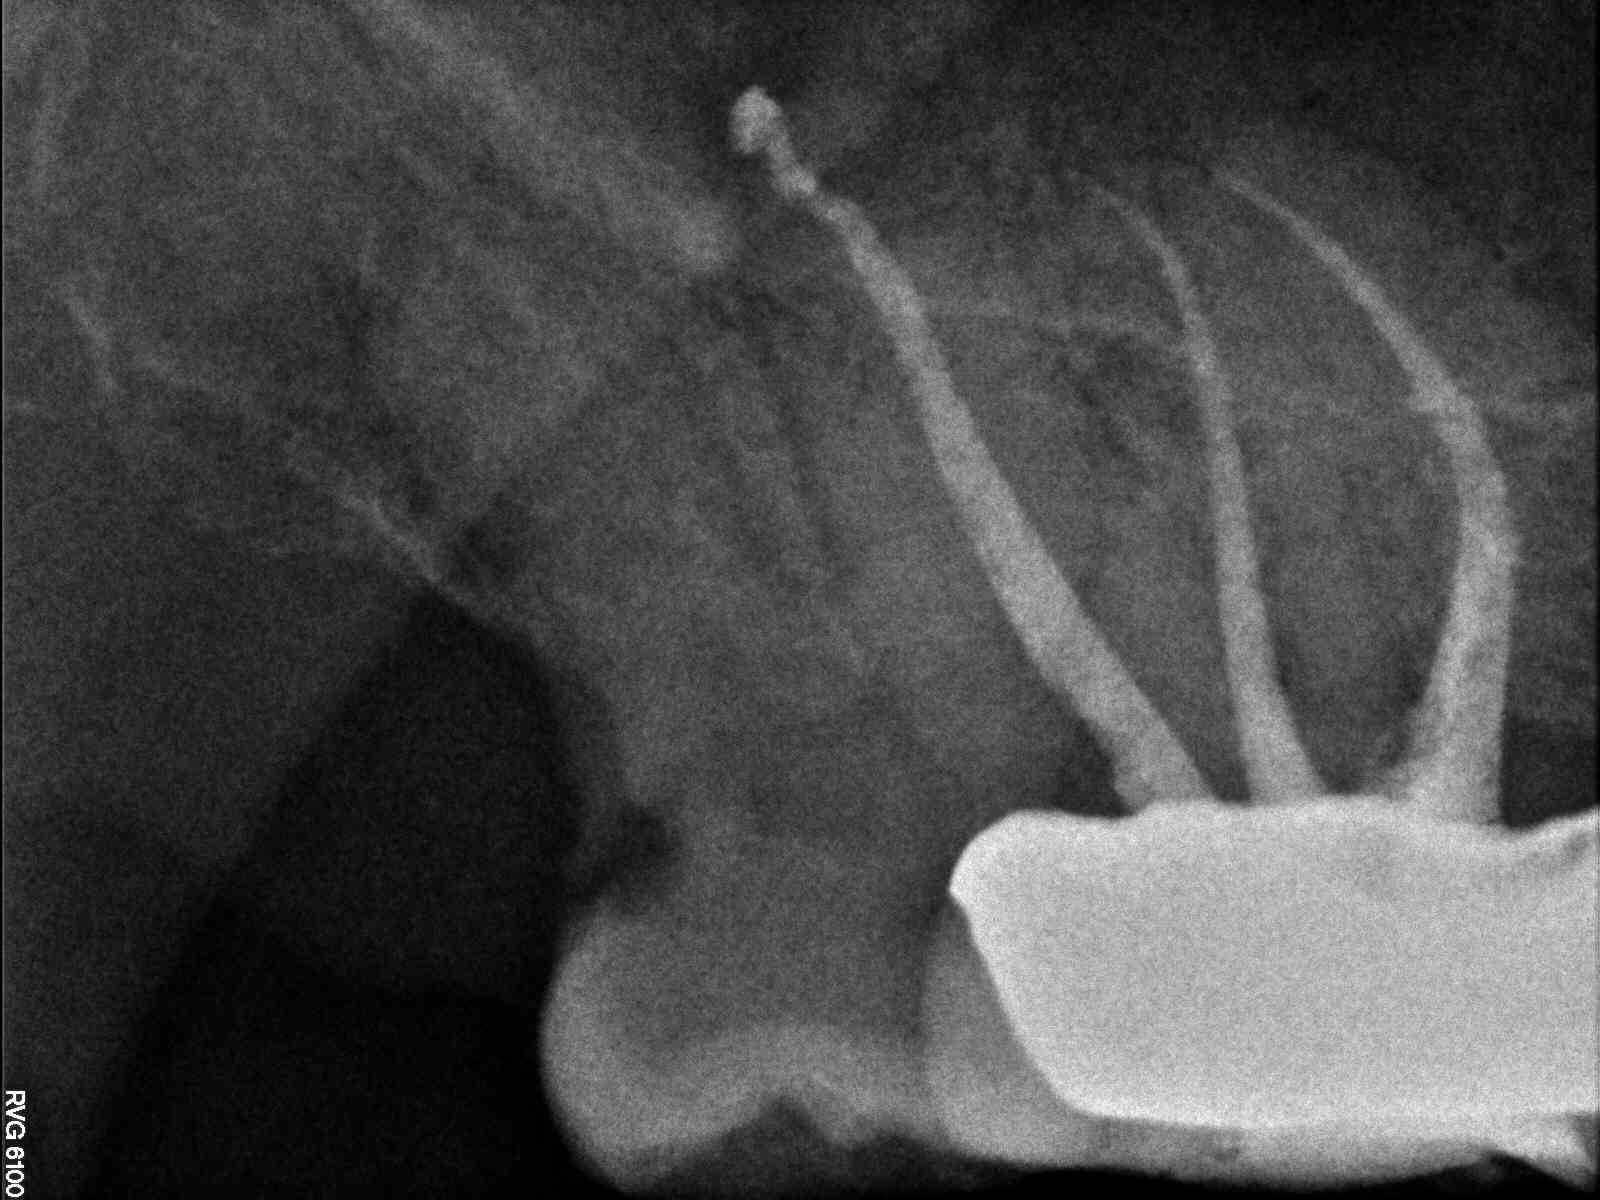

# (teeth with MB3 present- able to cleanse and shape the MB3) – (teeth

with MB2 present- able to cleanse and shape the MB2 – MB2 join

MB1 – teeth I consider calcified that no MB2 was found) – total # of 2nd

MB2 distance from MB1 – join MB1

NA – join in apical portion